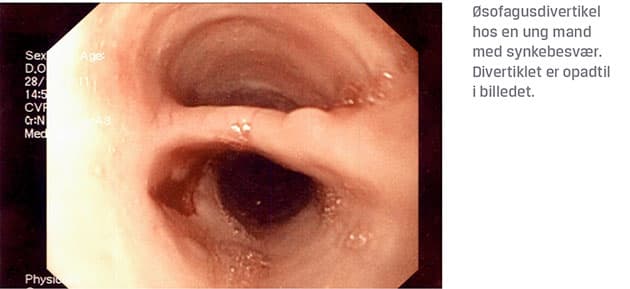

Affektion af de indledende faser, hvor ubehaget opstår umiddelbart efter indtagelse af føde, ofte ledsaget af hoste og regurgitation af bolus nasalt. Dette er forskelligt fra globusfornemmelsen, der er en konstant følelse af fylde eller klump i halsen, der ikke lindres ved synkning. Den orofaryngeale dysfagi dækker både mere åbenlyse årsager som infektion, fremmedlegeme i svælg eller spiserør, hvilket skal fjernes akut, og mere specielle årsager som f.eks. invert papillom [15], der strækker sig ned i mundsvælget og besværliggøre den mekaniske synkeproces. Halitose kan opstå pga. føderester i et divertikel – såsom Zenkers divertikel [16].